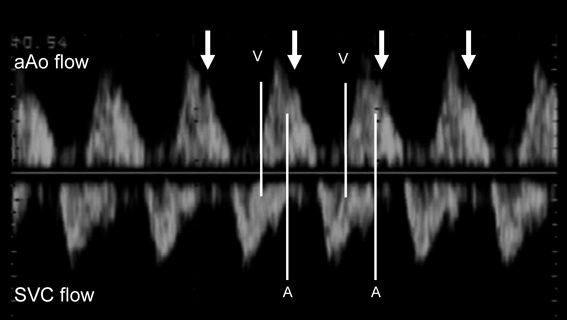

胎児不整脈は,徐脈性不整脈,頻脈性不整脈,およびその他の脈の不整の3つに大きく分類され1–3),この中で徐脈と頻脈のとき胎児心不全の評価が必要となる.徐脈性不整脈は,胎児心拍数が100回/分未満,頻脈性不整脈は200回/分以上と定義されることが多い.ただし,頻脈性不整脈では,急激な心拍数の変化などで不整脈の存在が示唆されるときには180回/分以上であれば頻脈性不整脈と定義している文献も多い.胎児期の不整脈診断は,主に心エコー検査によって行う.Mモード法(Fig. 1),ドプラ法による心房心室収縮を同時に評価する画像を描出し(Fig. 2),心房心室収縮の関連を見ることで不整脈の診断を行う1–3)

Pediatric Cardiology and Cardiac Surgery 35(4): 221-227 (2019)

Fig. 1 M-mode fetal echocardiogram in fetal atrial flutter

Simultaneous record of the left ventricle (LV) and the right atrium (RA) reveales 2 : 1 relation of atrial (white arrow) and ventricular contraction (hollow arrow). bpm, beats per minute; LA, left ventricle; RV, right ventricle.

Fig. 2 Fetal echocardiographic Doppler wave form of the simultaneous record of the superior vena cava (SVC) and the ascending aorta (aAo)

Right panel reveals the wave form of fetuses with normal sinus rhythm. Starting point of small reversal flow at SVC represents the timing of atrial contraction (A), and the starting point of forward flow at aAo represents the timing of ventricular contraction (V). The arrow reveals atrio-ventricular interval. IVC, inferior vena cava; LA, left atrium; RA, right atrium; RV, right ventricle.